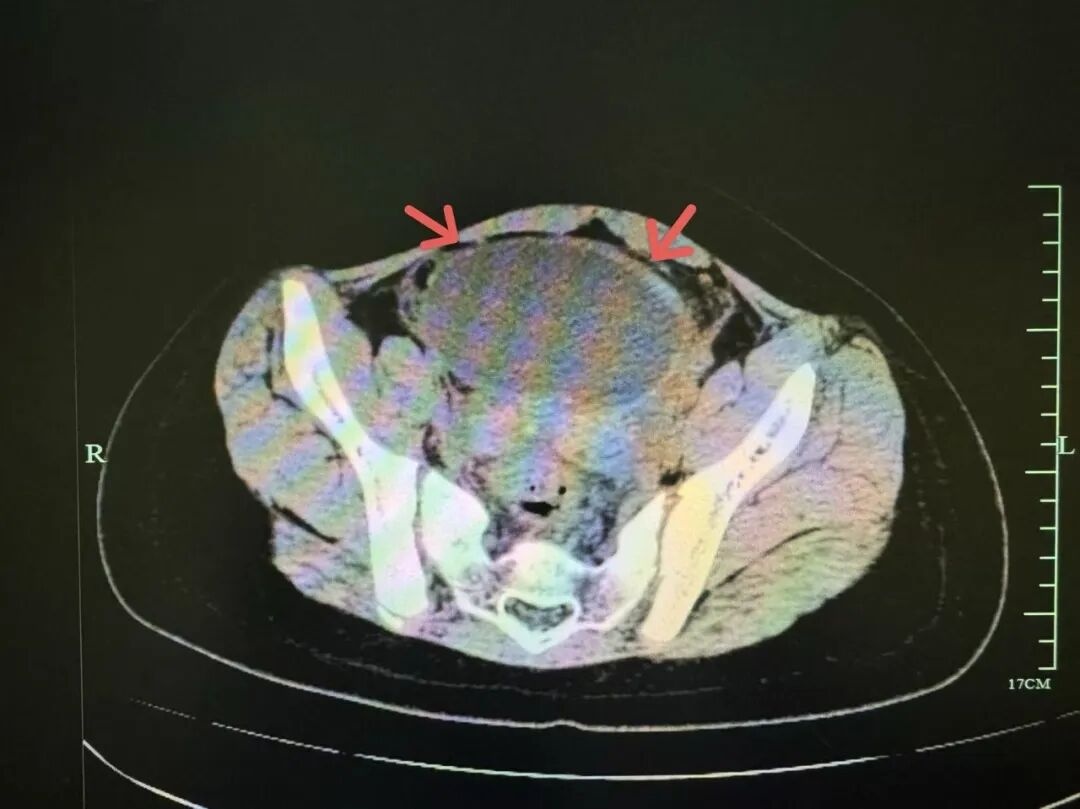

根据B超和CT显示,小吉的盆腔内有一个约9.5cm的巨大卵巢囊肿,并且已发生了 “蒂扭转”,这是一种需要紧急手术的妇科急腹症!浙江省中西医结合医院儿科主任詹璐告诉记者,“这个囊肿以前可能就有,那段时间小吉的学校里要每天做仰卧起坐,造成这个囊肿一点点扭过去了。”

(腔镜下照片)